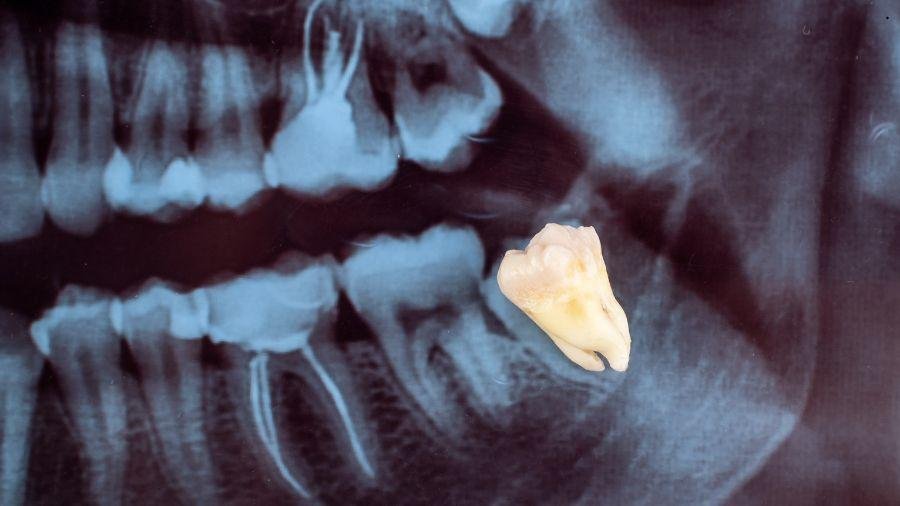

E se o dente que você arrancou pudesse salvar vidas? Para muita gente, a extração do siso é apenas o fim de um incômodo. Dor, inflamação, falta de espaço na arcada. O procedimento é comum, rápido e, na maioria das vezes, termina com o dente descartado como lixo hospitalar.

No interior do dente existe um tecido mole chamado polpa dentária. É ali que ficam vasos sanguíneos, terminações nervosas e, principalmente, células com alto potencial de regeneração.

Essas células-tronco são chamadas de células mesenquimais e possuem uma característica valiosa: a capacidade de se transformar em diferentes tipos de tecido, dependendo dos estímulos recebidos em laboratório.